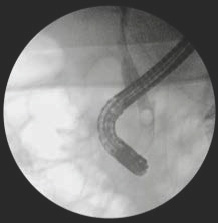

ERCP is a specialized procedure that combines the use of a side-viewing endoscope (a thin, flexible tube with a light and camera) called a Duodenoscope and X-rays to examine and treat conditions affecting the bile ducts and pancreatic ducts. These are the drainage tubes from your liver, gallbladder, and pancreas that lead into the first part of your small intestine (duodenum).

During ERCP, the endoscope is passed through your mouth, down your oesophagus (food pipe), through your stomach, and into the duodenum. A small plastic tube (catheter) is then passed through the endoscope into the openings of the bile and pancreatic ducts. A special dye (contrast medium) is injected into these ducts, which makes them visible on X-rays. This allows the George to see and treat abnormalities.

Large gallstone removed from the bile duct at ERCP